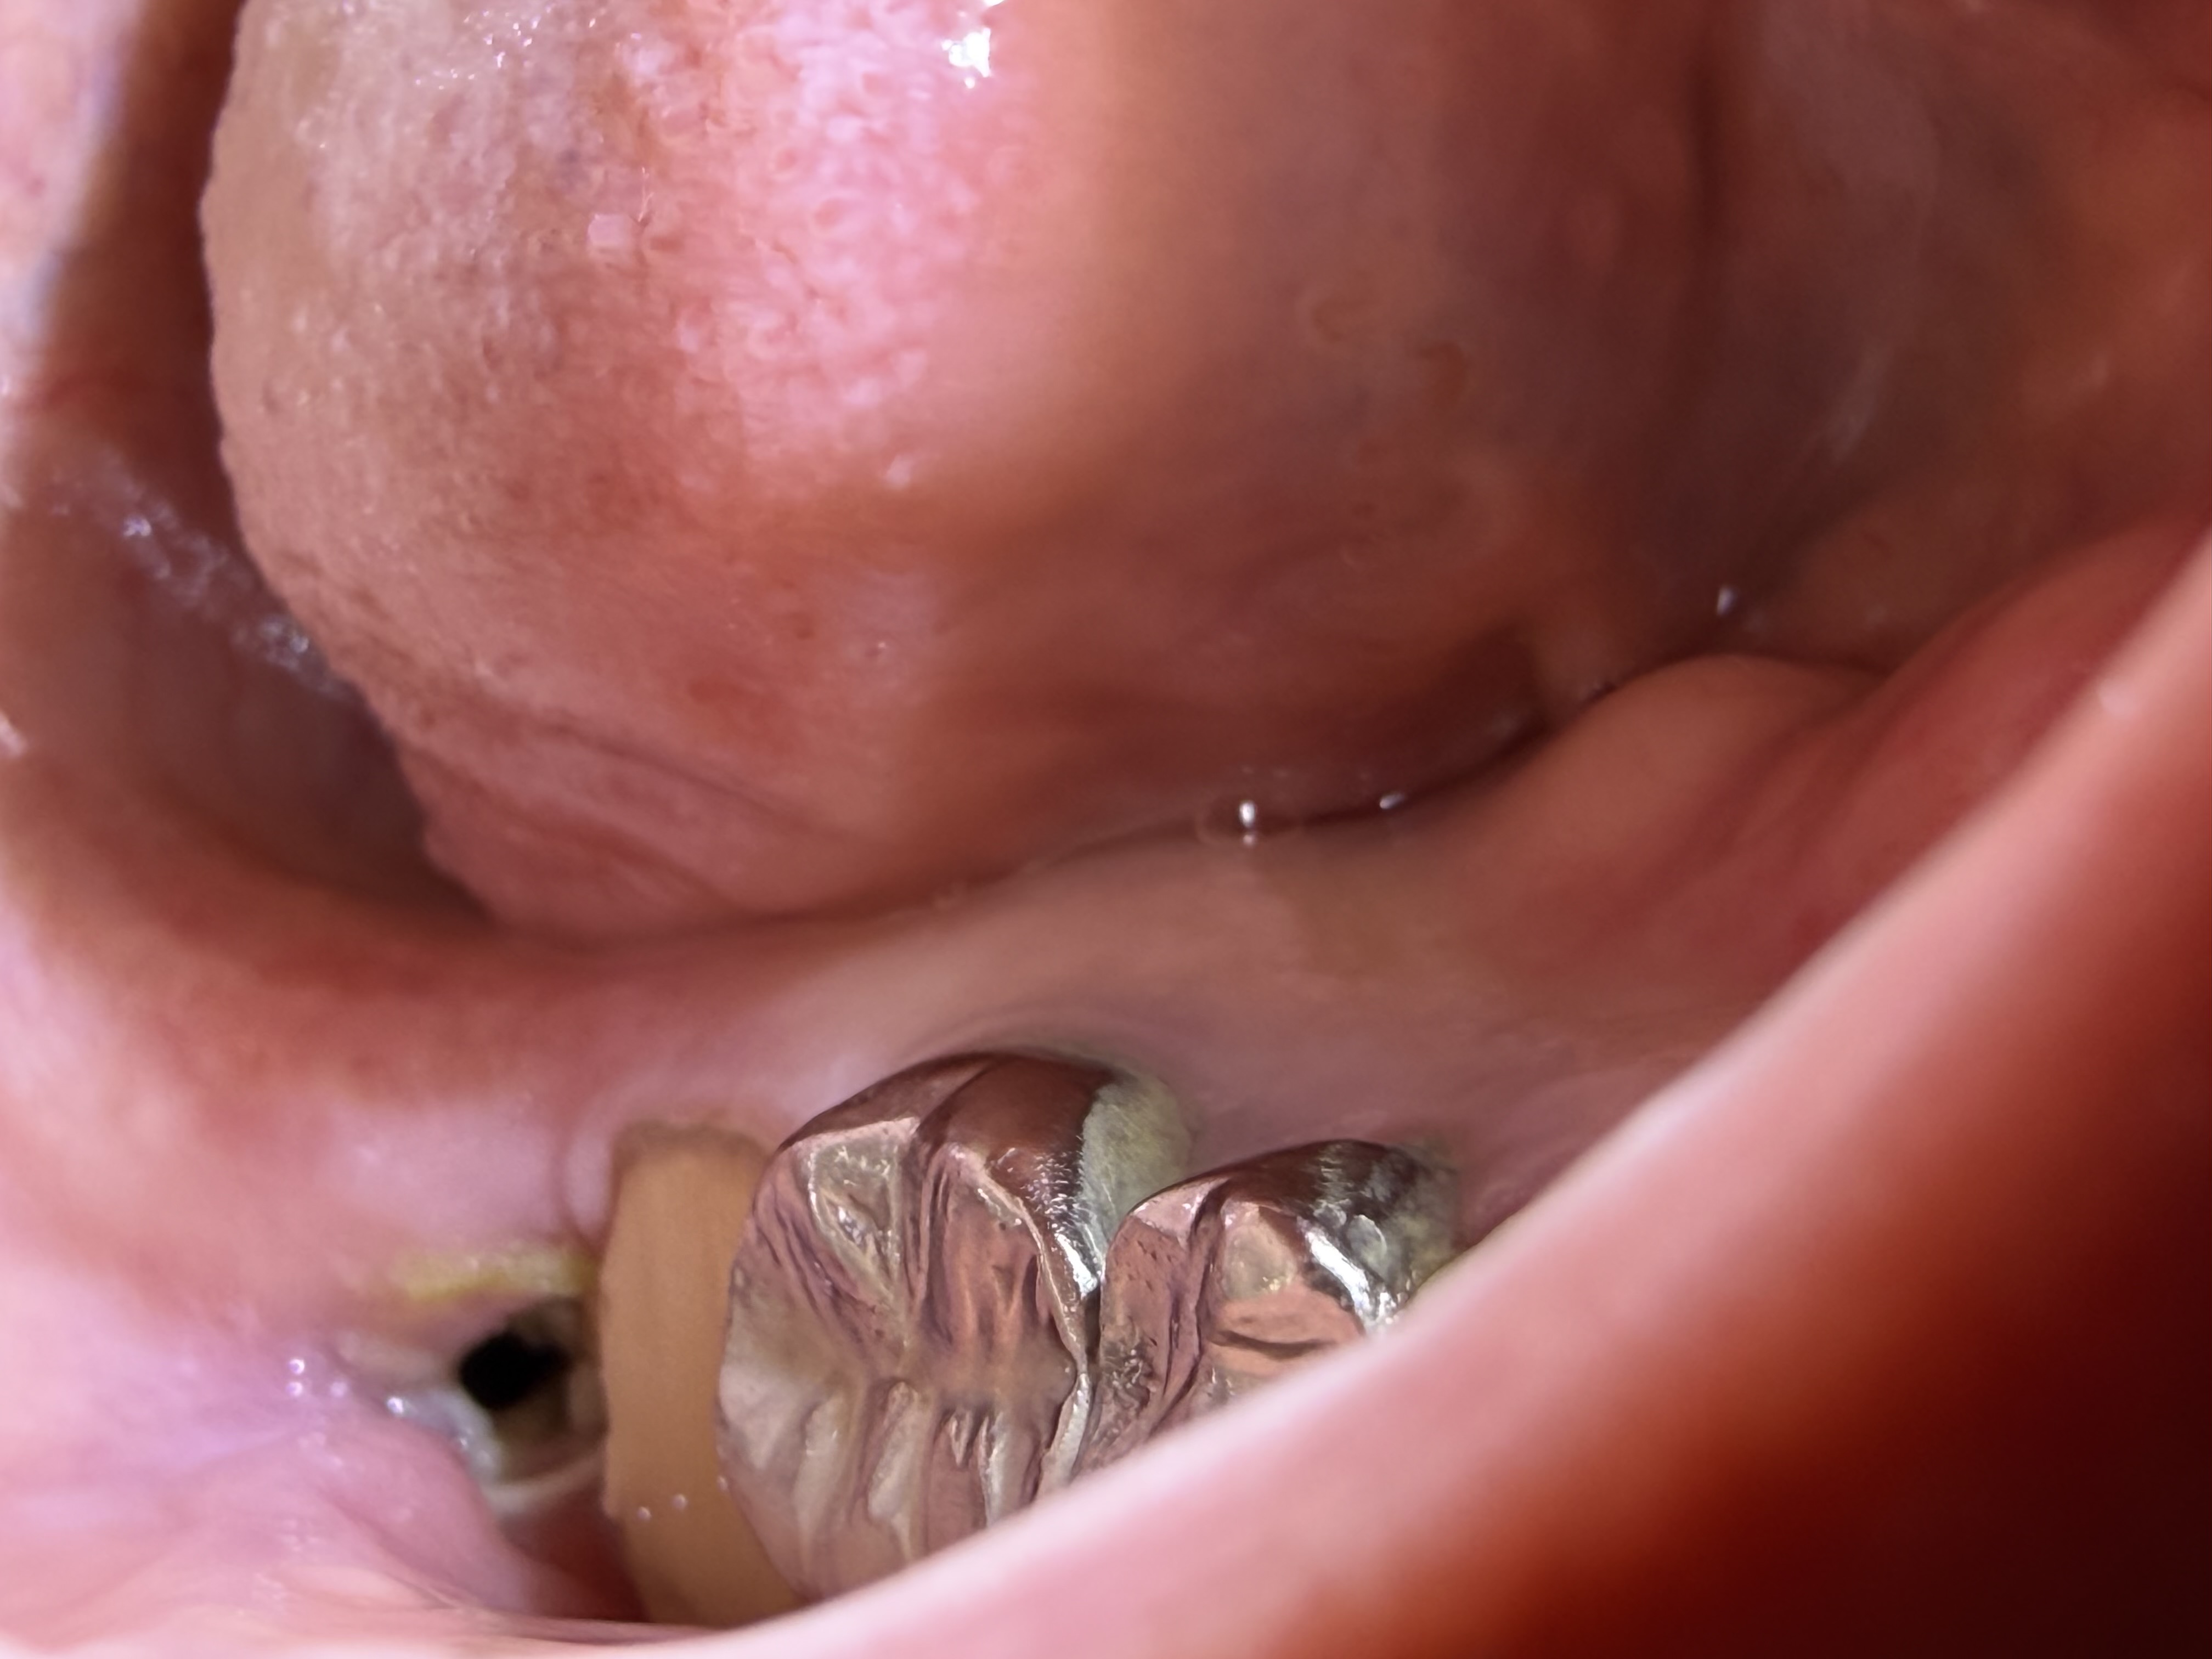

親知らず抜歯後、血餅がないように見えます。

親知らず抜歯後、歯茎の内側に硬いものがあります。